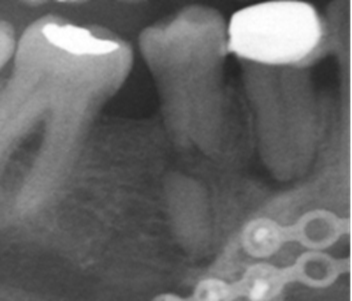

Los otros hallazgos analizados (Fig. 3) se presentaron en muy baja frecuencia. Para ninguno de los casos, se encontraron diferencias estadísticamente significativas entre hombres y mujeres.

Un hallazgo importante en este estudio fue encontrar que el 52,7 % de los dientes se consideraron subobturados, asociados en un 66% con lesiones apicales vs el 44.9 % en aquellos que estaban en límites de normalidad. Esto coincidiendo con De Moor y colaboradores 11 que encuentran que del 6,8 % de dientes que están obturados, el 56,6 % fueron considerados mal obturados. Un análisis utilizando tomografía de rayo de cono, mostró que el 23,04 % de dientes están mal obturados y en ellos el riesgo de tener una lesión apical aumenta en 4,38 veces17. Un estudio de Moreno y colaboradores18 mostró que el 51% de los dientes tratados, no presentaban patologías perirradiculares y solo el 33% se consideraron correctamente obturados.